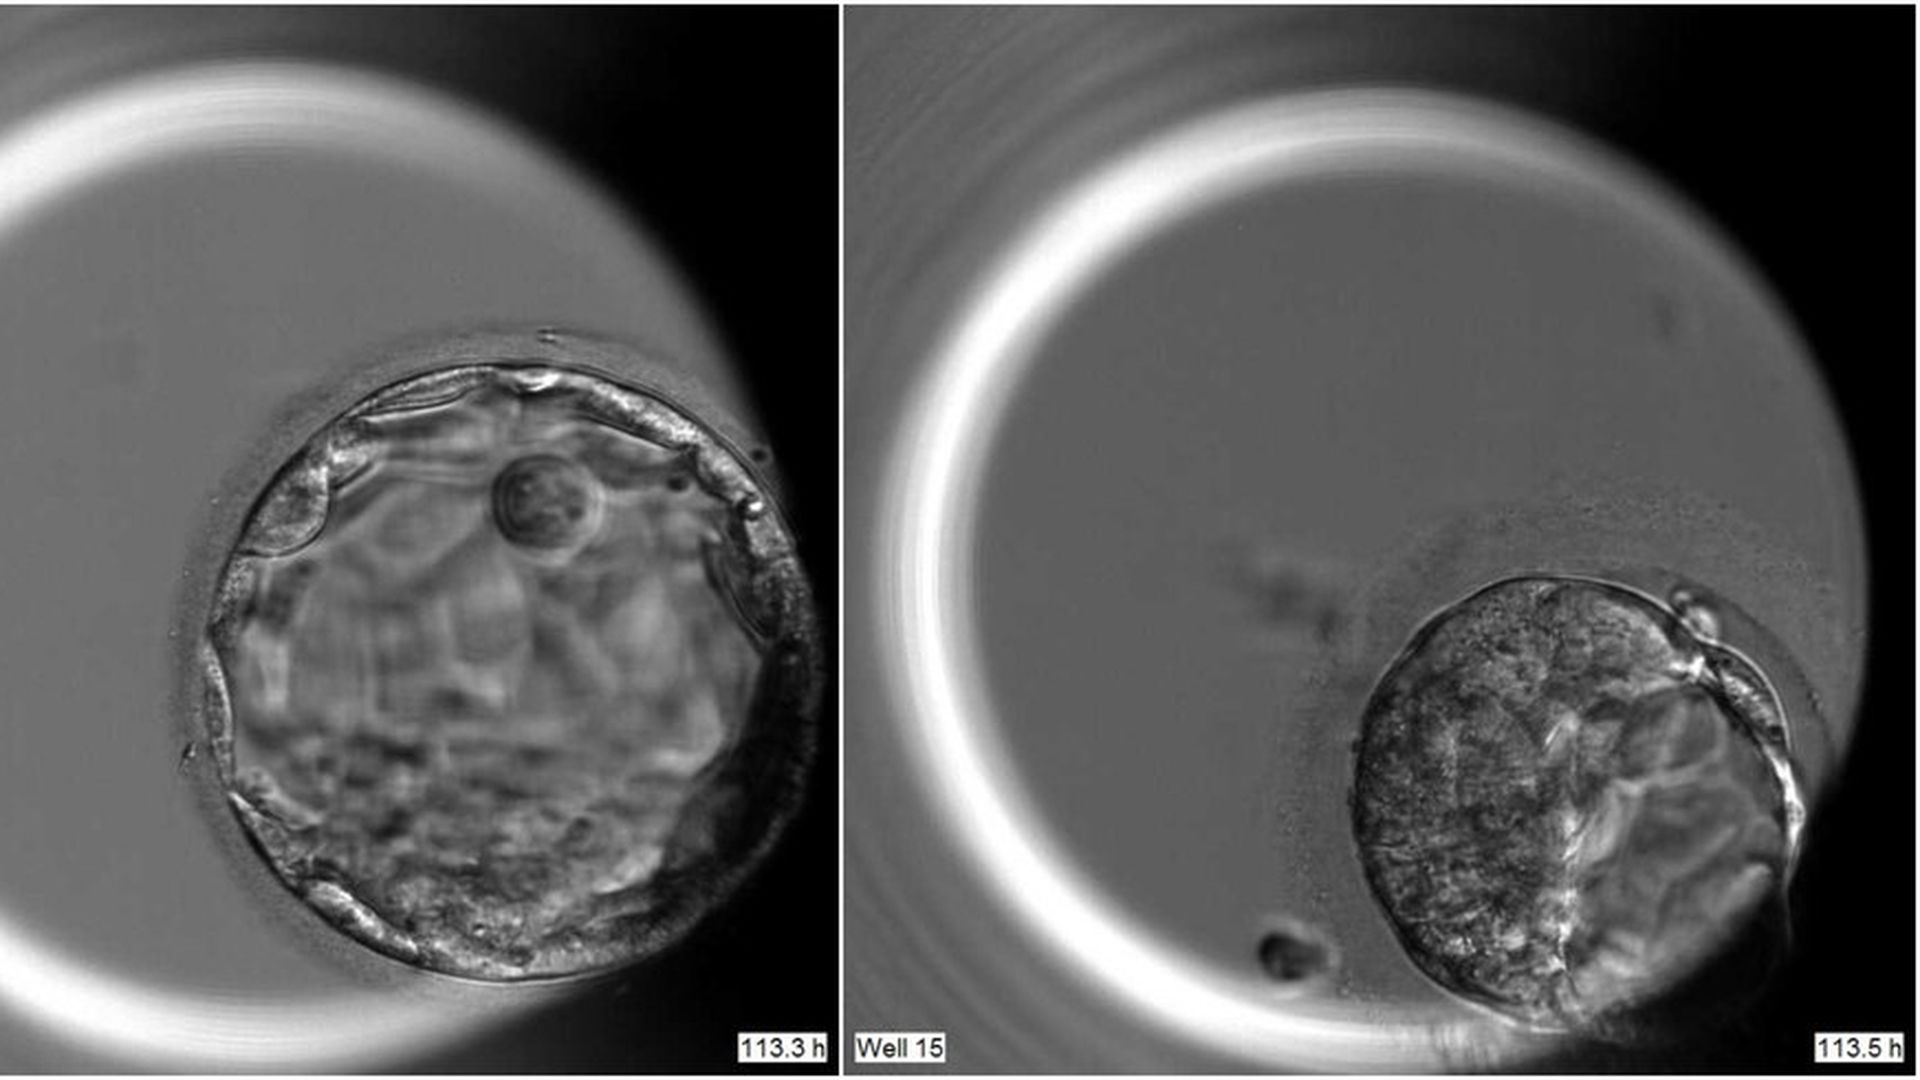

Эмбрион 4 аа

Эмбрион 4 аа 113 фотографий